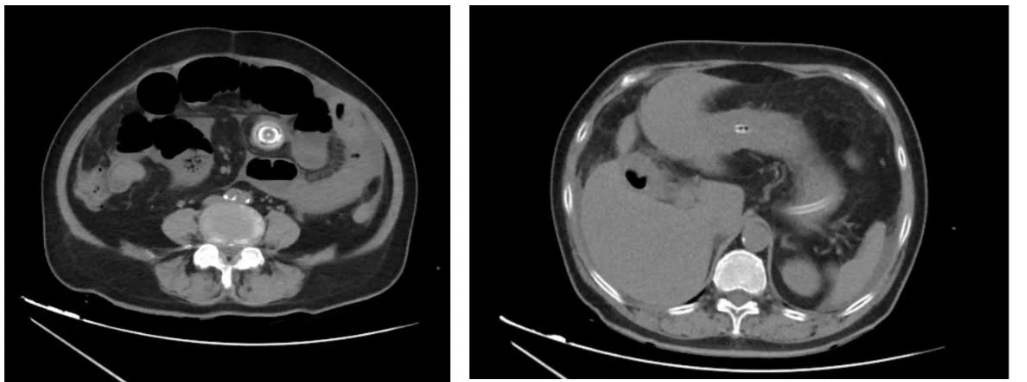

Hình ảnh sỏi mật của bệnh nhân qua chụp X.quang. Ảnh BVCC

Theo bác sĩ Vinh, tắc ruột do sỏi túi mật (gallstone ileus) là một trong những nguyên nhân hiếm gặp của tắc ruột cơ học. Biến chứng này xảy ra khi sỏi túi mật lâu ngày không điều trị gây viêm thủng túi mật vào tá tràng, sỏi di chuyển qua đường rò này xuống ruột và gây tắc nghẽn, chủ yếu ở hồi tràng của ruột non.

Nguyên nhân tắc ruột do sỏi mật chiếm khoảng 1-4% các trường hợp tắc ruột ở người lớn và lên đến 25% ở bệnh nhân trên 65 tuổi. Bệnh xuất hiện ở người già kèm theo nhiều bệnh nền sẽ làm trầm trọng thêm tình trạng lâm sàng và phức tạp trong lựa chọn phương án điều trị.